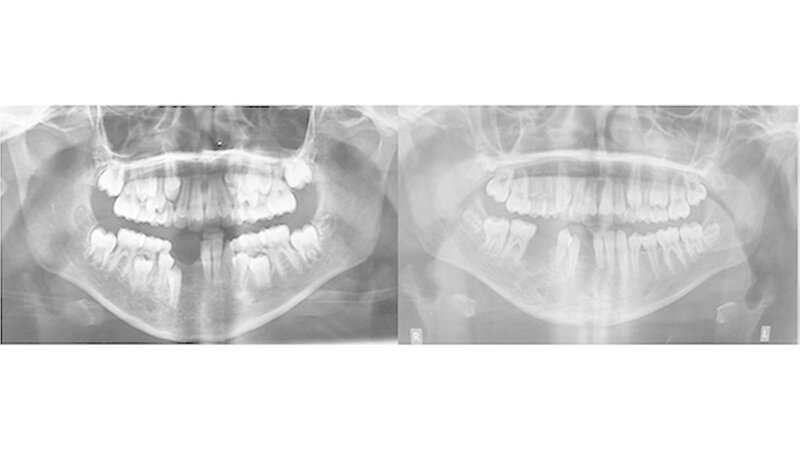

Ausgangssituation:Im Alter von 9 Jahren wurde die Patientin aufgrund gelockerter Zähne im vierten Quadranten des bleibenden Gebisses mit rezidivierenden Zahnfleischblutungen vorstellig. Die anschließend durchgeführte Diagnostik mit Probengewinnung bestätigte den Verdacht einer arteriovenösen Malformation.

Therapie und Verlauf:Trotz mehrfach primär durchgeführter Embolisationen mittels Polyvinylalkohol und Äthylen-Vinyl-Alkohol Copolymer (Onyx®) (Abb. 1) kam es zu einer Größenprogredienz des bestehenden Befundes mit Beteiligung der äußeren Haut submental (Abb. 2).

Auf Basis einer präoperativen computerassistierten Planung wurde eine Unterkieferteilresektion mit primärer Rekonstruktion mittels mikrovaskulärem Fibulatransplantat durchgeführt (Abb. 3). Die Patientin ist seitdem beschwerdefrei und es konnte keine weitere Progredienz des vorbestehenden Befundes beobachtet werden (Abb. 4).